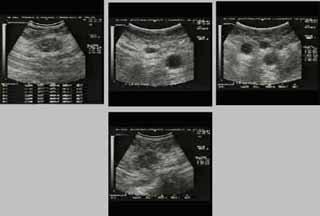

Οι απεικονίσεις των περιστατικών που επιδεικνύονται παρακάτω, έγιναν με κυρτές κεφαλές 3,5 και 5 ΜΗΖ, προκειμένου να φανεί, ότι και με τον εξοπλισμό αυτό, που σιγά-σιγά διαθέτουν όλο και περισσότερα ιατρεία, είμαστε σε θέση να έχουμε ικανοποιητικά αποτελέσματα.

Oι τελευταίες 4 απεικονίσεις έγιναν με ειδικό για μαστό ηχοβολέα linear, εναλλασσομένης συχνότητος 7,5-10ΜΗΖ.